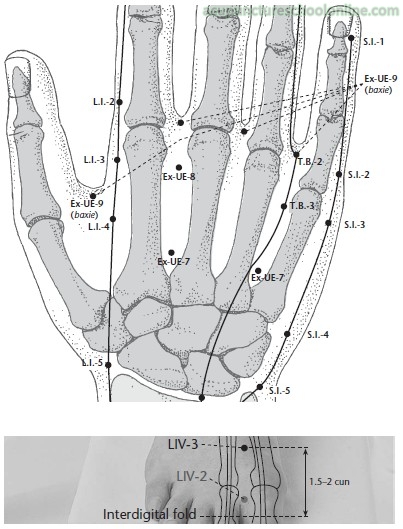

Often combined with Taichong Liv-3 to form the 4 gates, a common combination for moving stagnation causing pain and spasm anywhere in the body.

Basic information on location, needle depth, TCM actions, indications and combinations is taken from Deadman et al (2001): A Manual of Acupuncture with additional anatomical information researched by reference to Gray's Anatomy (38th Ed., 1995) unless otherwise referenced. Images were found on acupunctureschoolonline.com and can be traced back to Claudia Focks (2008) Atlas of Acupuncture originally. I cannot claim any credit or rights over them. Other sources should be quoted in the text.